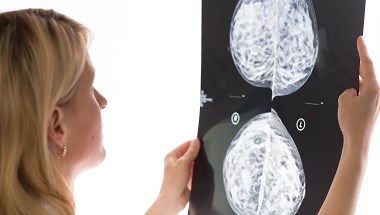

NICE recommends step-change targeted treatment for people with early breast cancer

Around 4,000 people are set to benefit from a step-change in treatment for early breast cancer following today’s (17 June 2022) provisional approval by NICE of abemaciclib in combination with hormone therapy as an option after surgery.